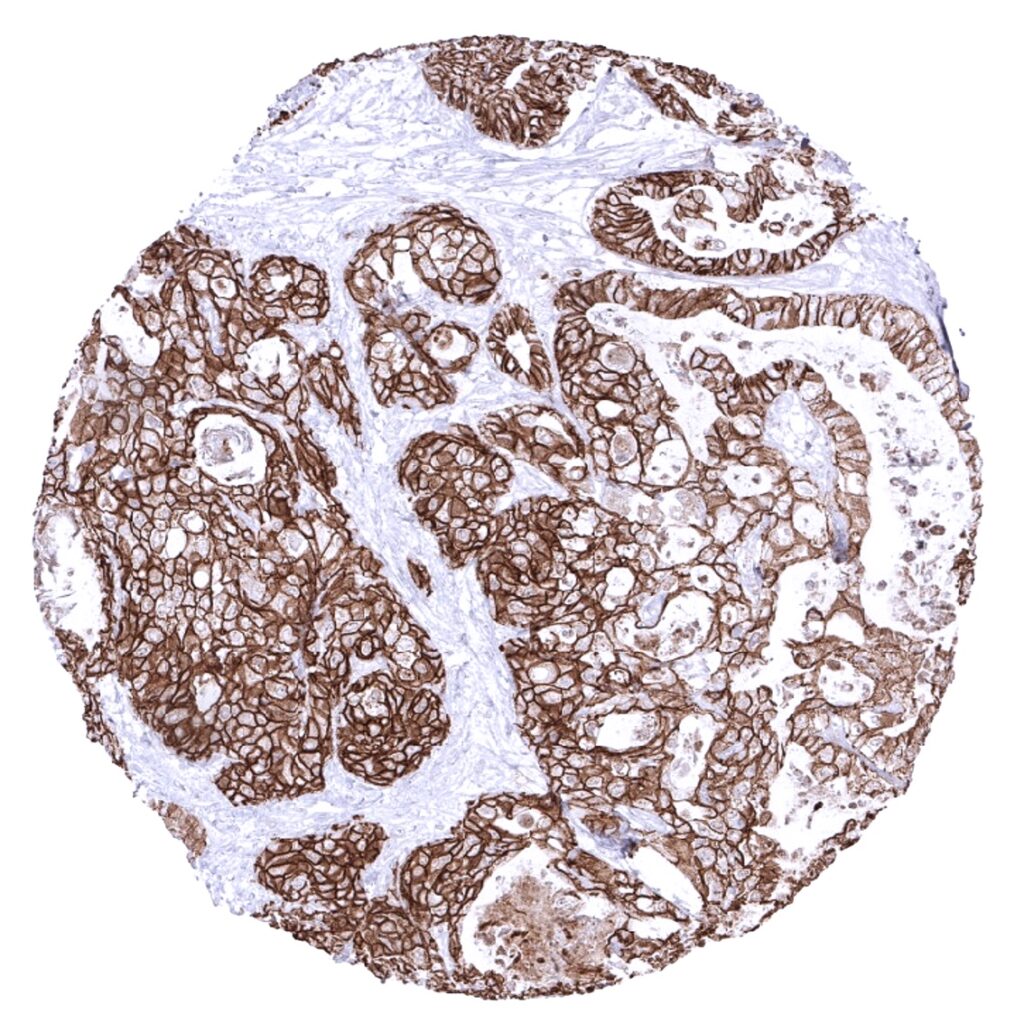

Kidney- Chromophobe renal cell carcinoma with strong membranous E-cadherin immunostaining.